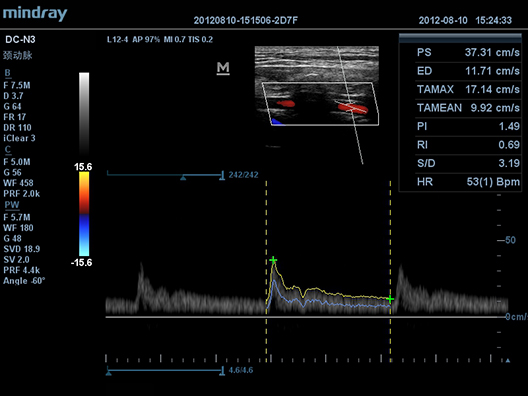

Auto IMT (–∞–≤—В–Њ–Љ–∞—В–Є—З–µ—Б–Ї–Њ–µ –Њ–њ—А–µ–і–µ–ї–µ–љ–Є–µ —В–Њ–ї—Й–Є–љ—Л –Ї–Њ–Љ–њ–ї–µ–Ї—Б–∞ –Є–љ—В–Є–Љ–∞-–Љ–µ–і–Є–∞)

–Р–≤—В–Њ–Љ–∞—В–Є—З–µ—Б–Ї–Њ–µ –Є–Ј–Љ–µ—А–µ–љ–Є–µ —В–Њ–ї—Й–Є–љ—Л –њ–µ—А–µ–і–љ–µ–є –Є –Ј–∞–і–љ–µ–є —Б—В–µ–љ–Ї–Є, –њ—А–µ–і–Њ—Б—В–∞–≤–ї—П—О—Й–µ–µ —В–Њ—З–љ—Г—О –Є–љ—Д–Њ—А–Љ–∞—Ж–Є—О –Њ —Б–Њ—Б—В–Њ—П–љ–Є–Є —Б–Њ–љ–љ–Њ–є –∞—А—В–µ—А–Є–Є.